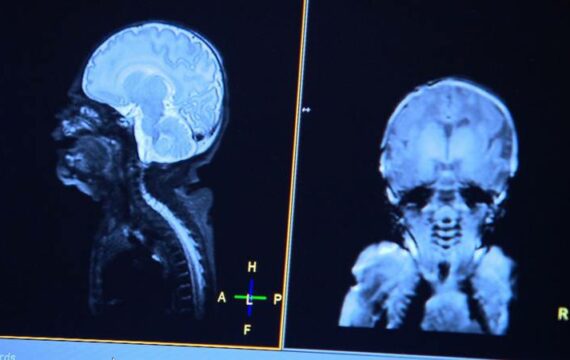

De ontwikkeling van het foetusbrein kon in beeld worden gebracht dankzij scans van zo’n honderd foetussen uit de Verenigde Staten. Aanstaande moeders die tussen de 20 en 39 weken zwanger waren, gingen met hun baby in de buik in een mri-scanner. Met een functionele MRI (fMRI) kun je 3d-beelden maken van gebieden met zuurstofrijk bloed in de hersenen. De aanwezigheid van zuurstofrijk bloed wijst op activiteit. Elise: “De gelijktijdige activiteit van meerdere hersengebieden wijst op samenwerking tussen die gebieden, op een actief netwerk. En we weten dat zo’n netwerk van actieve hersengebieden nodig is om complexe functies aan te sturen. Denk bijvoorbeeld aan een motorische functie als lopen of een cognitieve functie als lezen. Of een combinatie van beide, zoals spreken. Bij gezonde ongeboren kinderen is dit basisnetwerk in het brein dus al voor 60 procent aanwezig.”

Het onderzoek van Elise is onderdeel van het YOUth-onderzoek, een langlopend onderzoek in de regio Utrecht naar de ontwikkeling van 3000 kinderen tot in hun tienerjaren. Als onderdeel van YOUth Baby & Kind worden sinds twee jaar ook in Nederland mri-scans gemaakt van het brein van gezonde ongeboren baby’s. Daarmee kan het beeld van een normaal ontwikkeld foetusbrein verder verfijnd worden voor de Nederlandse situatie. Omdat de leefstijl en etnische achtergrond van de Amerikaanse vrouwen kunnen afwijken, kan dit invloed hebben op de hersenontwikkeling van hun kinderen.

Voor haar promotieonderzoek volgt Elise nu honderd zwangere Nederlandse moeders en hun kinderen. Er zullen mri-scans gemaakt worden bij 30-33 weken zwangerschap en binnen vier weken na de geboorte. Elise: “Ik ben blij dat zoveel moeders hieraan willen meewerken. Door MRI-onderzoek te doen tijdens én na de zwangerschap kunnen we de hersenontwikkeling over langere tijd bekijken, zodat we nog meer inzicht en vergelijkingsmateriaal krijgen voor te vroeg geboren kinderen.” Een mri-scan tijdens de zwangerschap is volkomen veilig. Er is geen sprake van ongezonde straling zoals röntgenstraling.